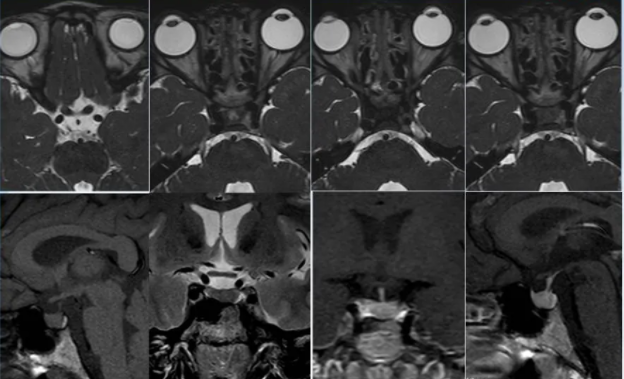

鞍区胶质瘤具有比较典型的MRI特点,具体表现包括:

1.肿瘤体及较大,分叶状。多无瘤周水肿

2.囊实性或实性,囊性部分常位于肿瘤前下部,实性部分内多见散在小囊变区

3.T1W1上肿瘤呈稍长或长T1信号。T2W1上呈稍长和长T2信号,增强后肿瘤无明显强化。

此外,患者就诊时多有眼部症状,而无下丘脑及垂体内分泌异常症状。鞍区胶质瘤MRI影像结合其临床发病特点,有助于提高术前正确诊断率。